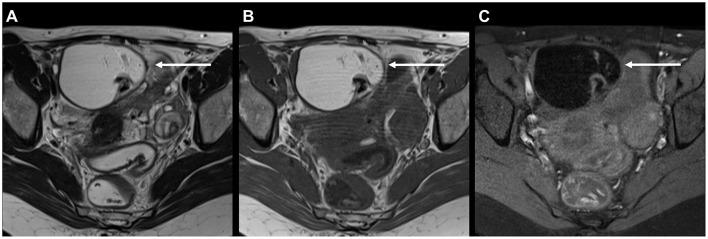

303 consecutive patients (mean age, 33.4 years ± 8.3) were evaluated. Incidental findings were noted in 299/303 (98.7%) patients. Most frequently, ossification of the hip acetabular rim and degenerative changes of the lumbar spine were noted. In 25/303 (8.3%) patients, incidental findings had high clinical significance. For specific incidental findings, significantly higher prevalences were found in patients with than in patients without evidence of deep infiltrating endometriosis on MRI (hip acetabular rim ossification, = 0.041; annulus fibrosus fissures, = 0.006; gallstones, = 0.042).

共评估了303例连续患者(平均年龄33.4岁±8.3岁)。299/303例(98.7%)患者有偶然发现。最常见的是髋关节髋臼缘骨化和腰椎退行性改变。25/303例(8.3%)患者的偶然发现具有较高临床意义。对于特定的偶然发现,MRI显示有深部浸润性子宫内膜异位症证据的患者患病率显著高于无该证据的患者(髋关节髋臼缘骨化,P = 0.041;纤维环裂隙,P = 0.006;胆结石,P = 0.042)。